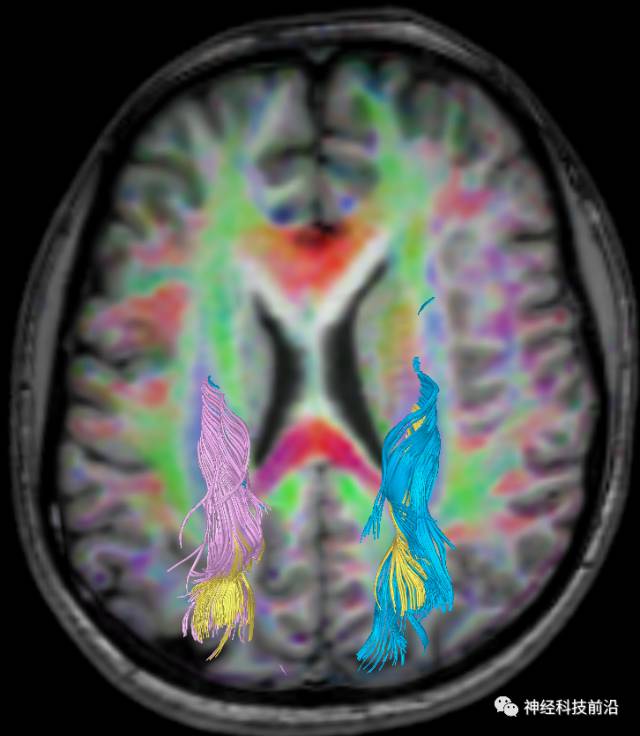

下面为皮质脊髓束的走形及位置

皮质脊髓束与皮质脑桥束的关系毗邻